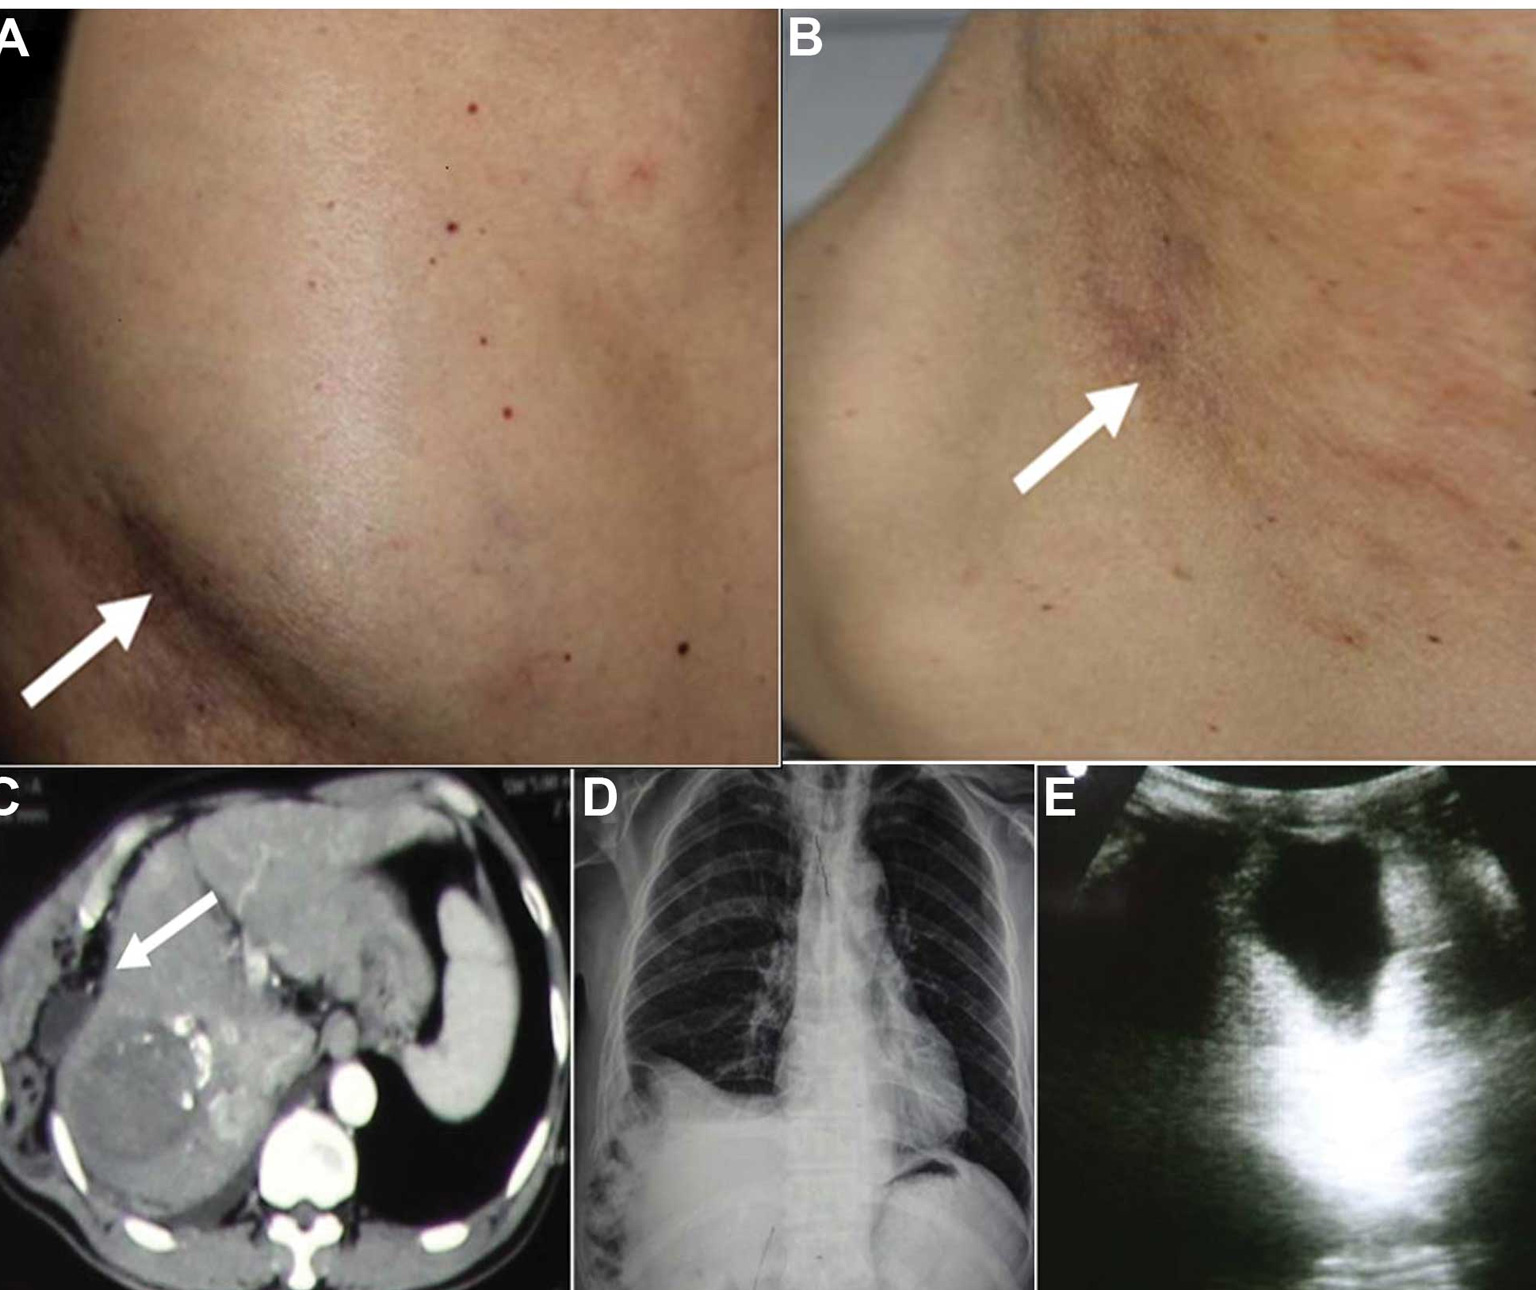

The diagnosis of chest wall tumors typically involves a combination of imaging studies, such as X-rays, CT scans, or MRI scans, to visualise the tumour and assess its extent. A biopsy, which involves taking a small sample of the tumour for examination under a microscope, is often performed to determine whether the tumour is benign or malignant.